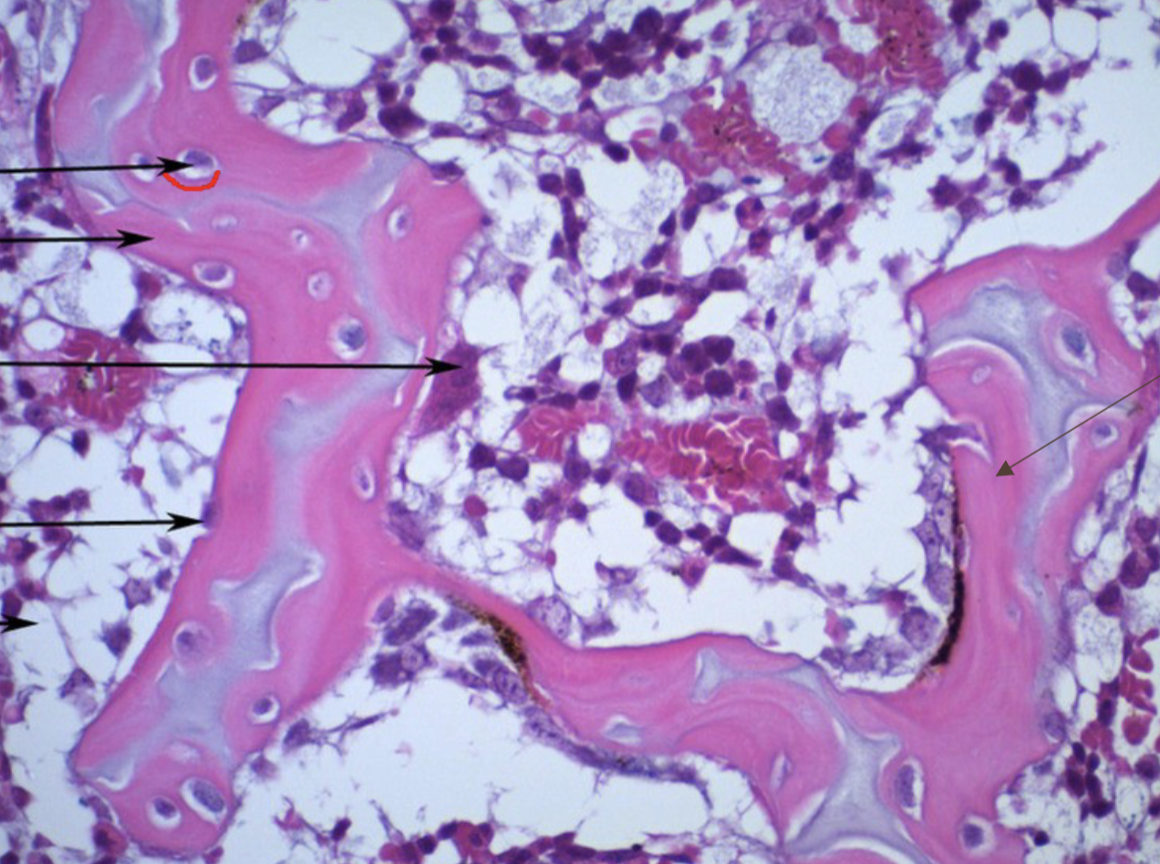

<p>spongey bone</p>

spongey bone

• cancellous

• porous, lattice like structure

• provides strength and reduces weight

• inner most bone type

• made of trabeculae: thin rods of bone that run parallel with stressor

osteon

modular unit of bone

central canal of osteon

• hole in the middle of osteon

• houses blood vessels and nerves in dense bone tissue

• typically runs vertically

osteocytes of osteon

• mature bone cells

• respond to stress on bone and remodel bone in response

lacunae of osteon

• small cavities that contain mature bone cells

• houses osteocytes

canaliculi of osteon

• thin tubes that connect lacunae

• provides passageway through dense bone material

3 types of lamellae:

• concentric

• interstitial

• circumferential

concentric lamellae

cylindrical layers of bone matrix that surround central haversian canal

interstitial lamellae

irregularly shaped bone tissue remains that fill spaces between osteons

circumferential lamellae

thin, flat layers of bone matrix that wrap completely around the circumference of bone shaft